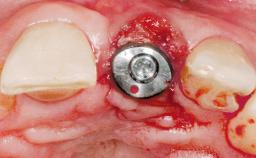

Immediate Placement of an Implant in a Maxillary Right Central Incisor Site

A 30-year-old female patient was referred to the office for the treatment of tooth 11. Her chief concern at the initial visit was to inquire, “Why is my tooth pink?” Upon clinical examination, it was determined that tooth 11 had a previous history of trauma and that the clinical crown had become noticeably pink in color as a result of internal resorption. This diagnosis was confirmed radiographically, indicating a large radiolucency involving the central and distal portions of the clinical crown. It was determined that restoration of this tooth was not possible, and that extraction was indicated. The presence of a mid-line diastema, which the patient wanted to reproduce, directed the treatment plan for tooth replacement utilizing a dental implant.

| Type of Implants | One-Piece|Reduced-Diameter |

| Bone Augmentation | Horizontal|Simultaneous |

| Augmentation Materials | Autogenous chips|Membrane |

| Placement Protocol | Immediate implant placement |

| Tooth Site | Maxillary incisor or canine |

| Socket Morphology | Single-root socket |

| Socket Integrity | Sufficient, with intact bone walls |

| Bone Volume | Sufficient, with intact walls |